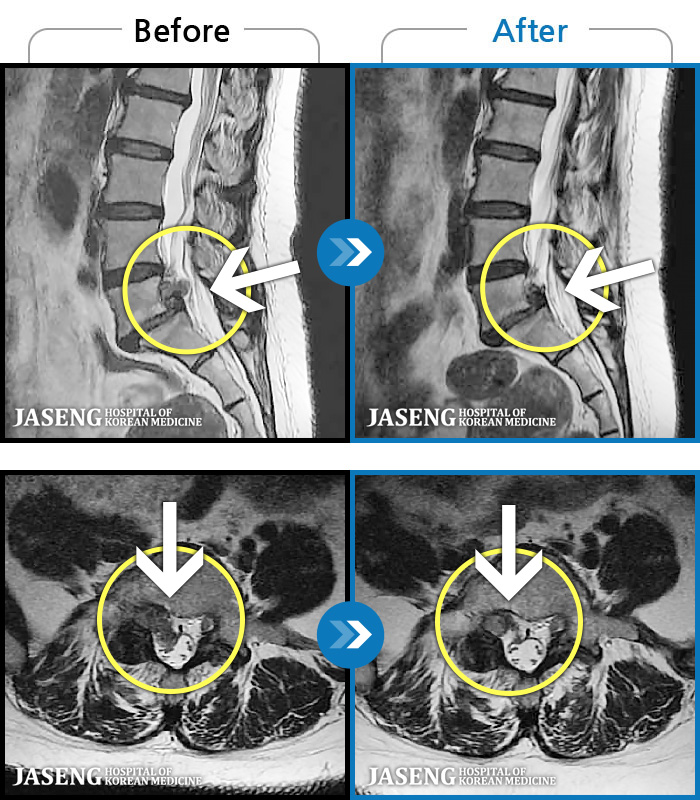

MRI ġ

1,237 MRI ũ ʸ Ȯϼ.